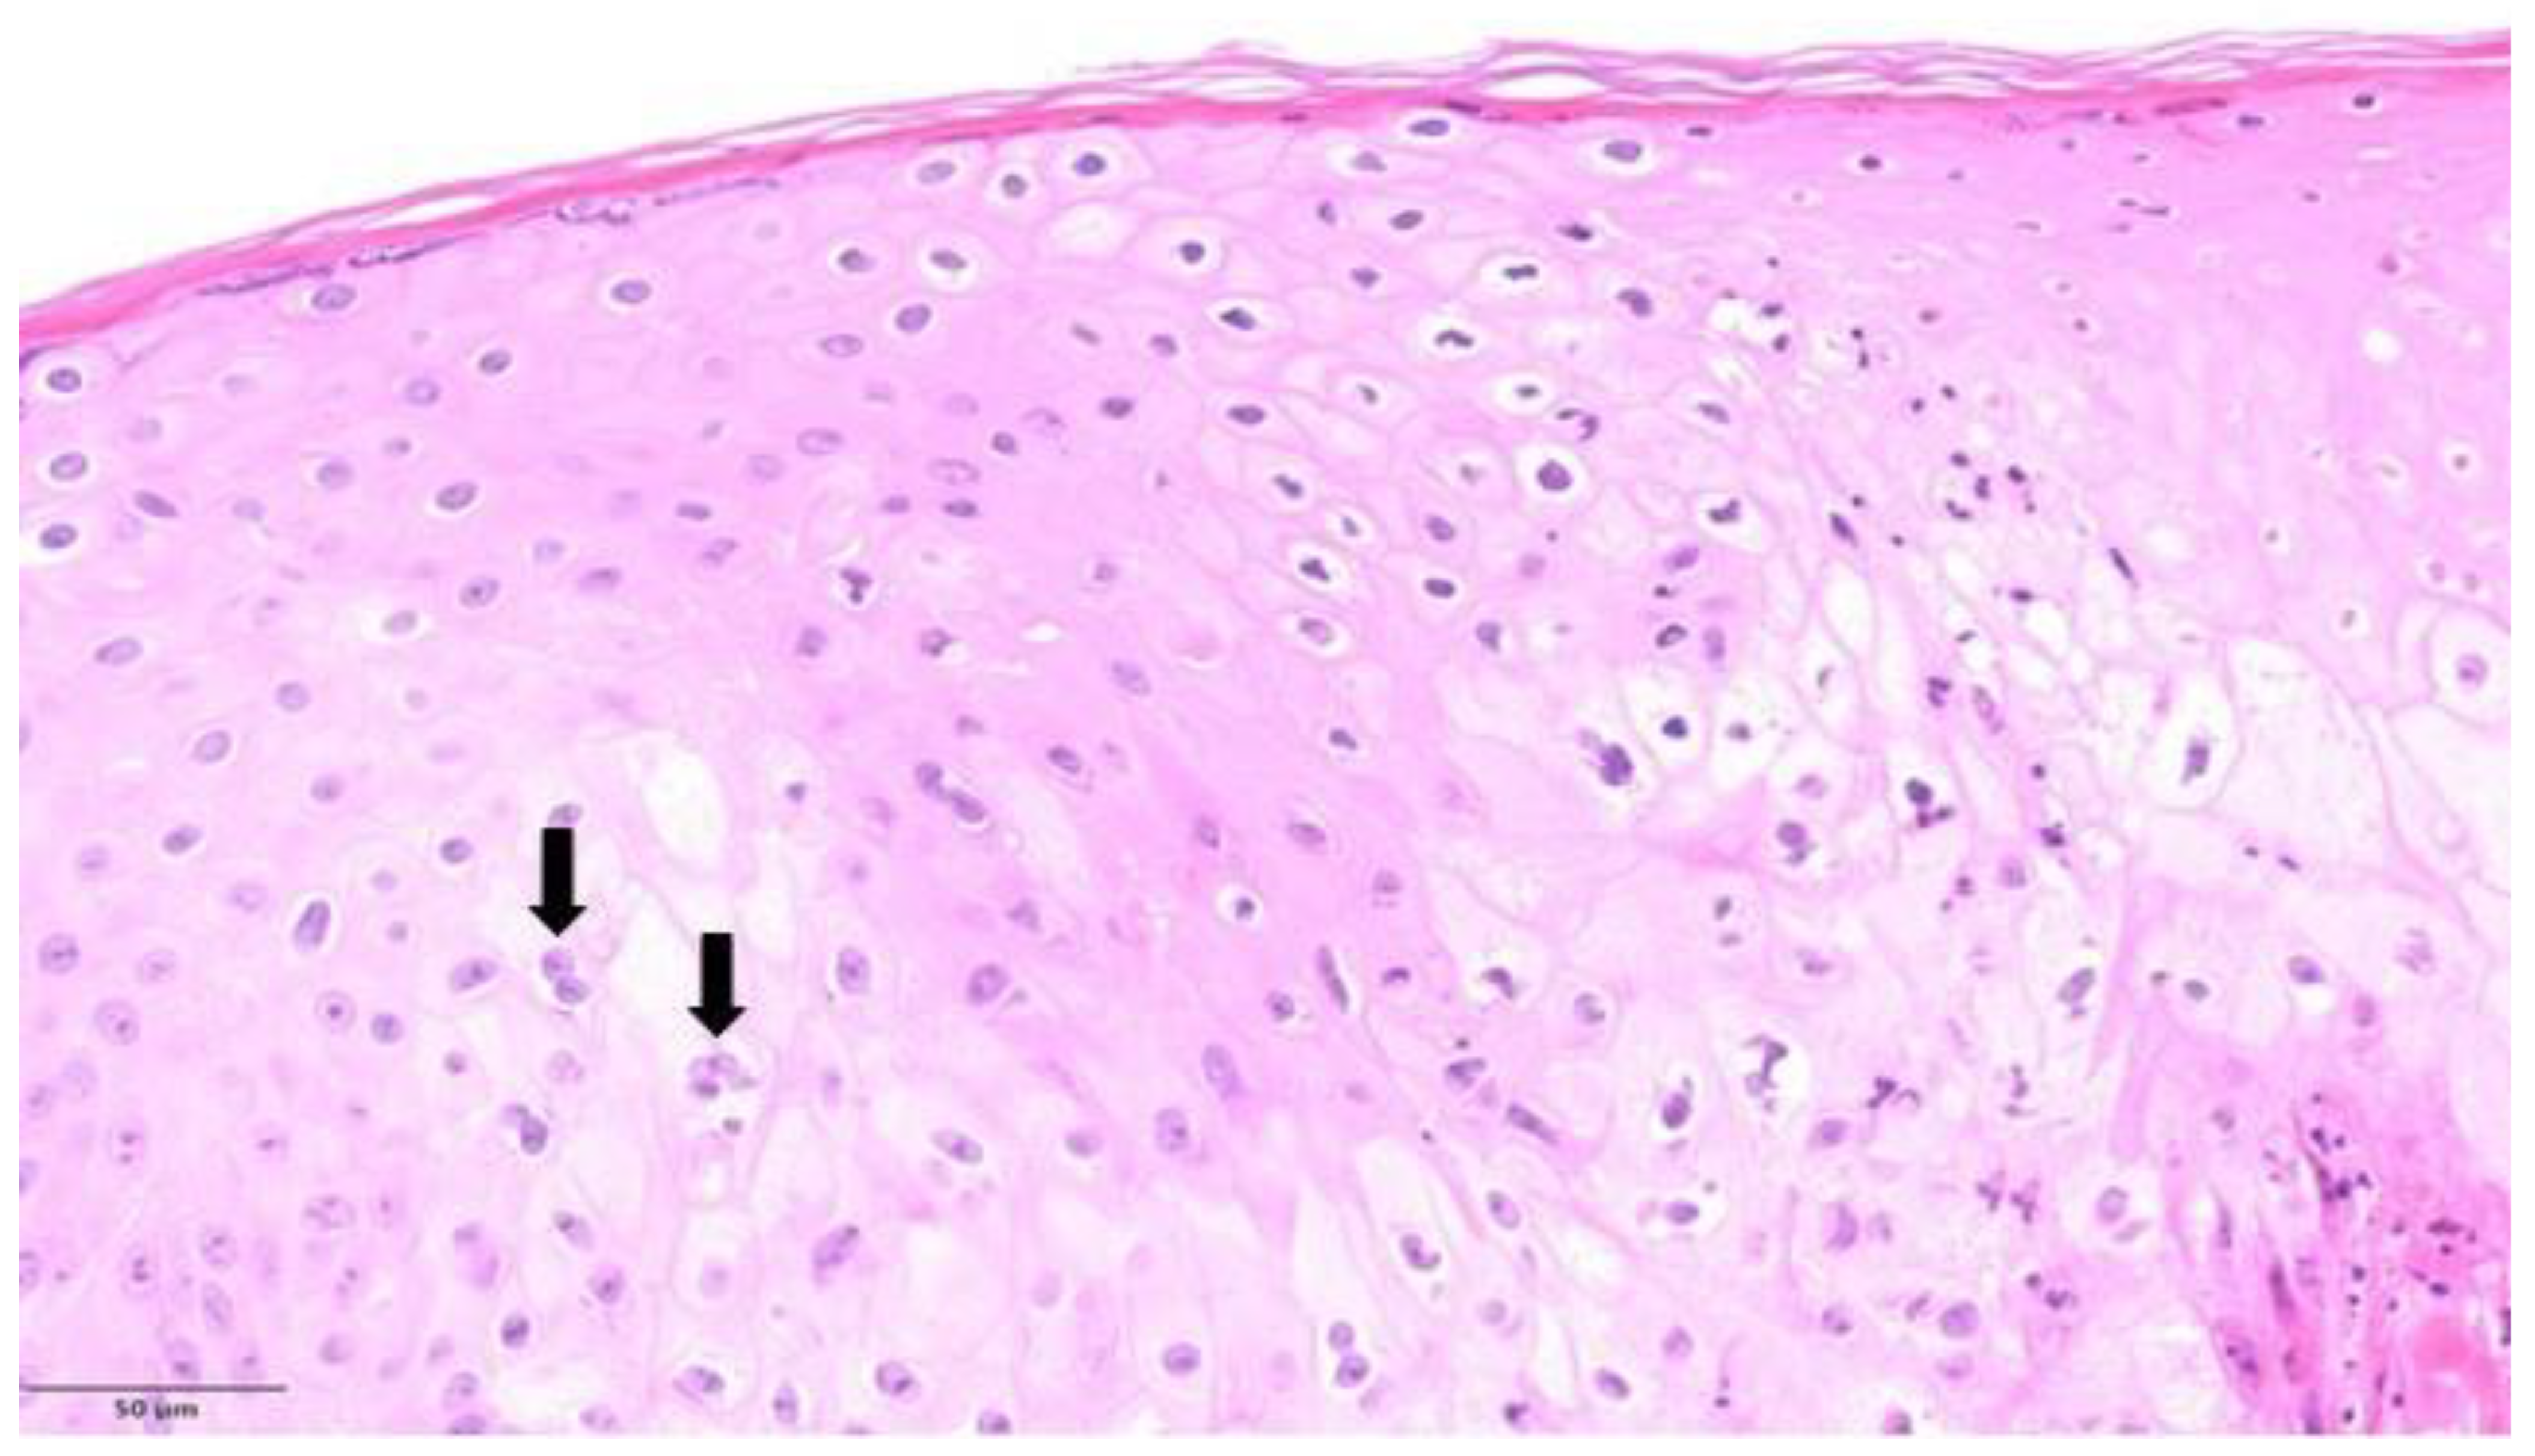

| 1 | Left thigh; penile shaft | Pustular stage | Multinucleated keratinocytes; occasional Guarnieri bodies; extensive ballooning; ground glass nuclei; degenerative modifications in the acrosyringial epithelium | Moderate perivascular and periadnexal with neutrophils |

| 2 | Penile | Pustular stage | Ground glass nuclei; ballooning; degenerative modifications in follicular keratinocytes | Mild perivascular lymphocytic infiltration |

| 3 | Groin, left shoulder | Pustular stage | Ballooning; occasional Guarnieri bodies; degenerative modifications in follicular keratinocytes | Moderate perivascular and periadnexal with neutrophils |

| 5 | Pubic region | Vesicular stage | Ballooning; spongiosis and achantosis; degenerative modifications in the acrosyringial epithelium | Severe perivascular, interstitial, and periadnexal with neutrophils |